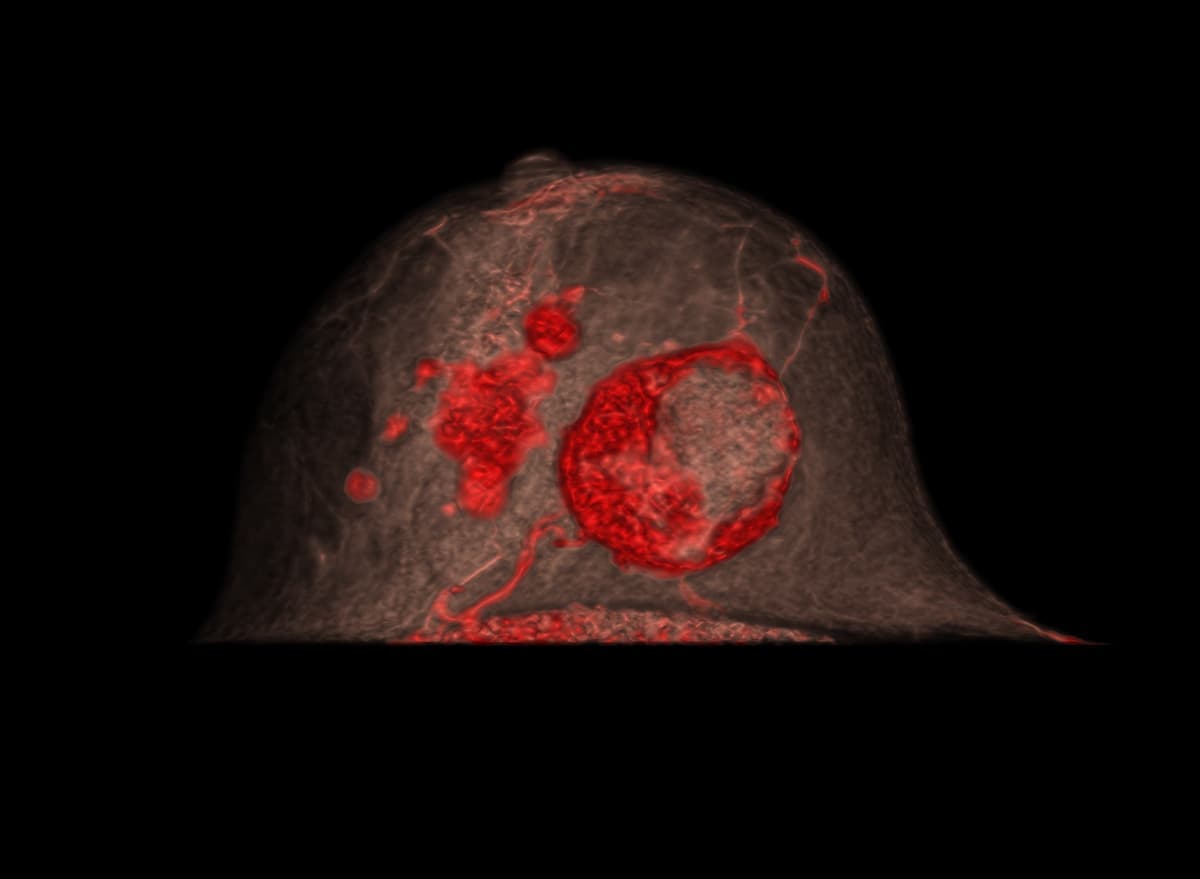

多発性乳がん

患者背景

• 70~79歳の女性で、右乳房に触知可能な腫瘤を認める。

• 過去のマンモグラフィでは単一の腫瘤のみが描出されていた。

• 超音波検査では、病変は円形かつ境界明瞭で、嚢胞性と固形成分を伴っていた。さらに、滑らかで不規則な辺縁を有する複数の低エコー性病変が検出された。

多発性乳がんの疑いを確認するため、乳腺CT検査を実施した。

画像詳細

• 造影前:円形の腫瘤性病変で、中心部に低吸収(壊死/液体)領域を認める。画像所見は複数の病変を疑わせる。

• 造影後:触知可能な腫瘤は造影剤を不均一に増強します。乳房の複数の象限に、不規則な縁と滑らかな縁を有する複数の造影増強腫瘤が明示されています。

評価:BI-RADS 5

画像提供:エヴリン・ヴェンケル医学博士(エルランゲン大学病院)

多発性乳がん画像